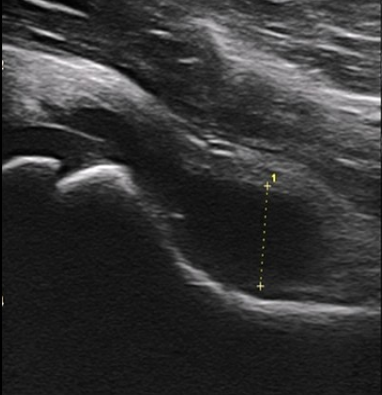

Identify this image.

Transient arthritis seen as effusion in joint